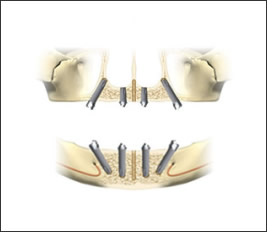

All-on-4によるインプラントの配置

インプラントを斜めに埋め込むことにより、噛む力をインプラント上に広く均等に配分できます。